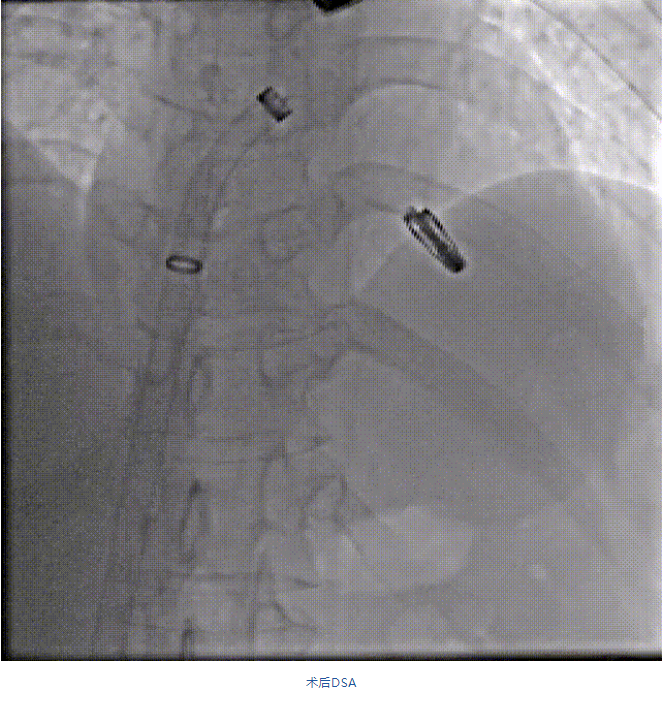

在阜外醫(yī)院潘湘斌教授團隊的支持下,手術(shù)經(jīng)股靜脈-房間隔入路,采用全身麻醉插管,在TEE和DSA引導(dǎo)下完成房間隔穿刺。置入JensClip瓣膜夾系統(tǒng)后,在左房調(diào)整瓣膜夾的位置和軸向,后進入左室,在TEE引導(dǎo)下捕捉二尖瓣前后瓣葉,并關(guān)閉瓣膜夾。經(jīng)TEE反復(fù)確認(rèn)手術(shù)效果后最終鎖定并釋放瓣膜夾。術(shù)后即刻超聲顯示瓣膜夾位置穩(wěn)定,功能良好,二尖瓣反流由術(shù)前4+減少至微量,手術(shù)圓滿成功。